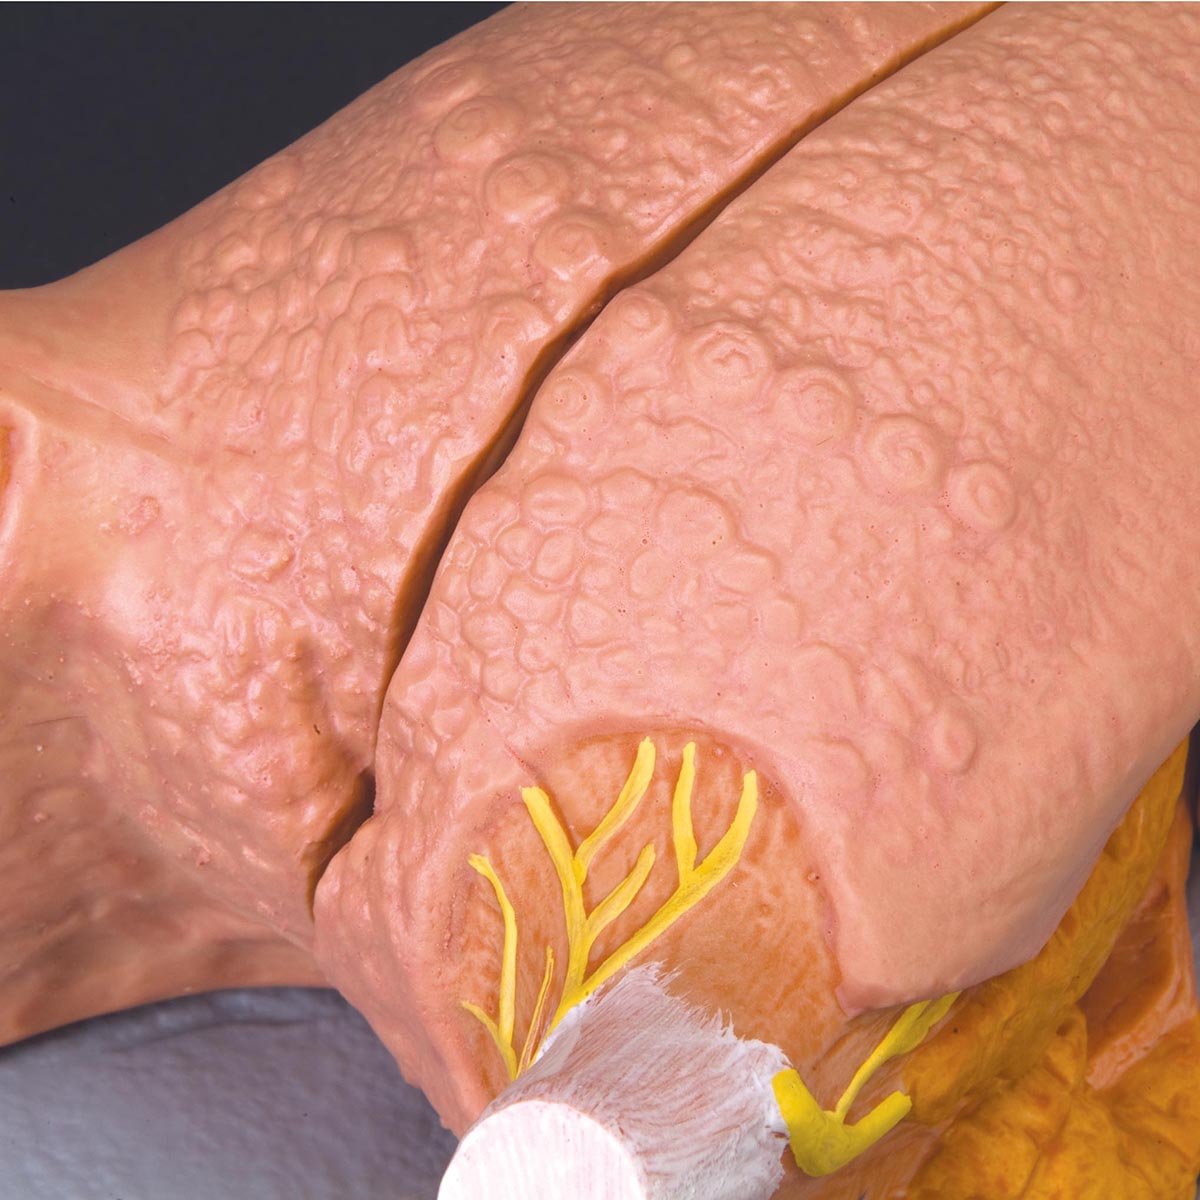

Salg af anatomiske modeller er det bærende element i eAnatomi, selvom vi også bruger mange ressourcer på at udvikle vores egne anatomiske materialer som fx plakater. Anatomiske modeller anvendes til forskellige formål og kan både vise afgrænset væv, organer samt organsystemer. Søger du en simpel model af knoglevæv eller måske en avanceret torso-model baseret på MRI teknologi, kan du finde det hele på eanatomi.com.